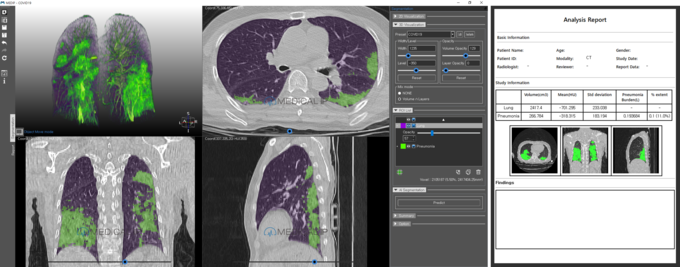

전 세계적으로 코로나 의심환자와 확진자 수가 급증하는 가운데 조기 진단과 중증도 판단은 매우 중요한 화두로 떠올랐다. 코로나19 CT 분석 AI 소프트웨어는 메디컬아이피 홈페이지 (www.medicalip.com)를 통해 누구나 무료로 다운로드 받을 수 있으며 코로나 19 환자의 CT 영상을 분석해 1분 내외로 코로나 폐렴을 자동으로 탐지, 분할, 정량화한다. 이를 통해 폐렴이 심한 중증 환자의 선별과 모니터링에 기여를 할 것으로 기대된다.